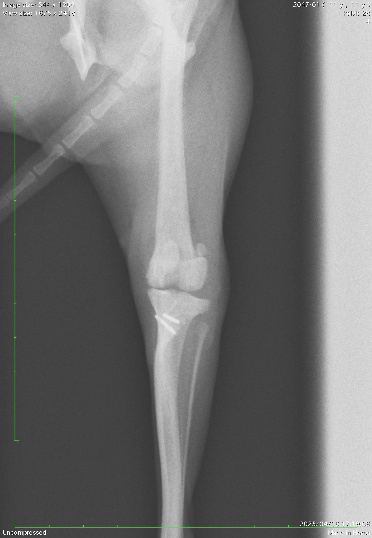

2.X線検査

X線画像を撮影し、脱臼方向の確認や大腿骨と脛骨の骨格変形の有無、変形性膝関節症及び前十字靭帯断裂の併発の有無を確認します。

本症例の術前X線検査所見

本症例は触診と合わせ、膝蓋骨内包脱臼GradeⅡ:症状ありと診断致しました。